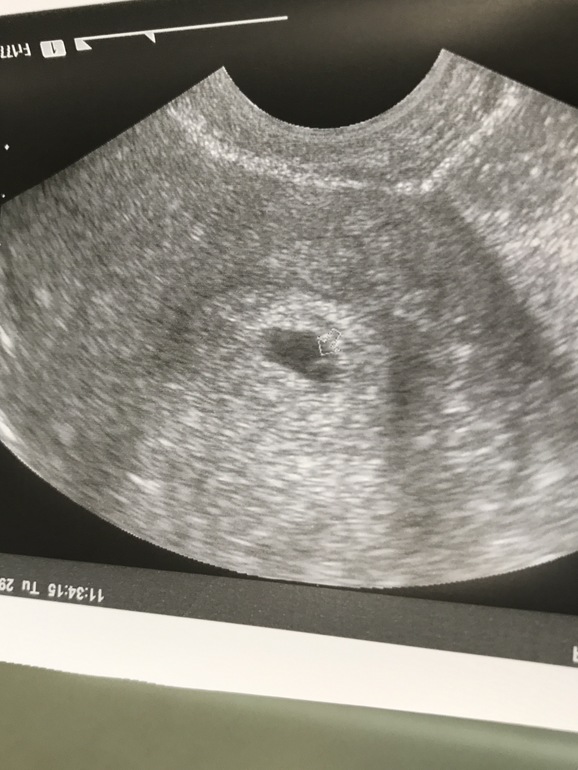

4-5 недель

ну и фоточка